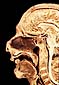

Pared Medial de las Fosas Nasales